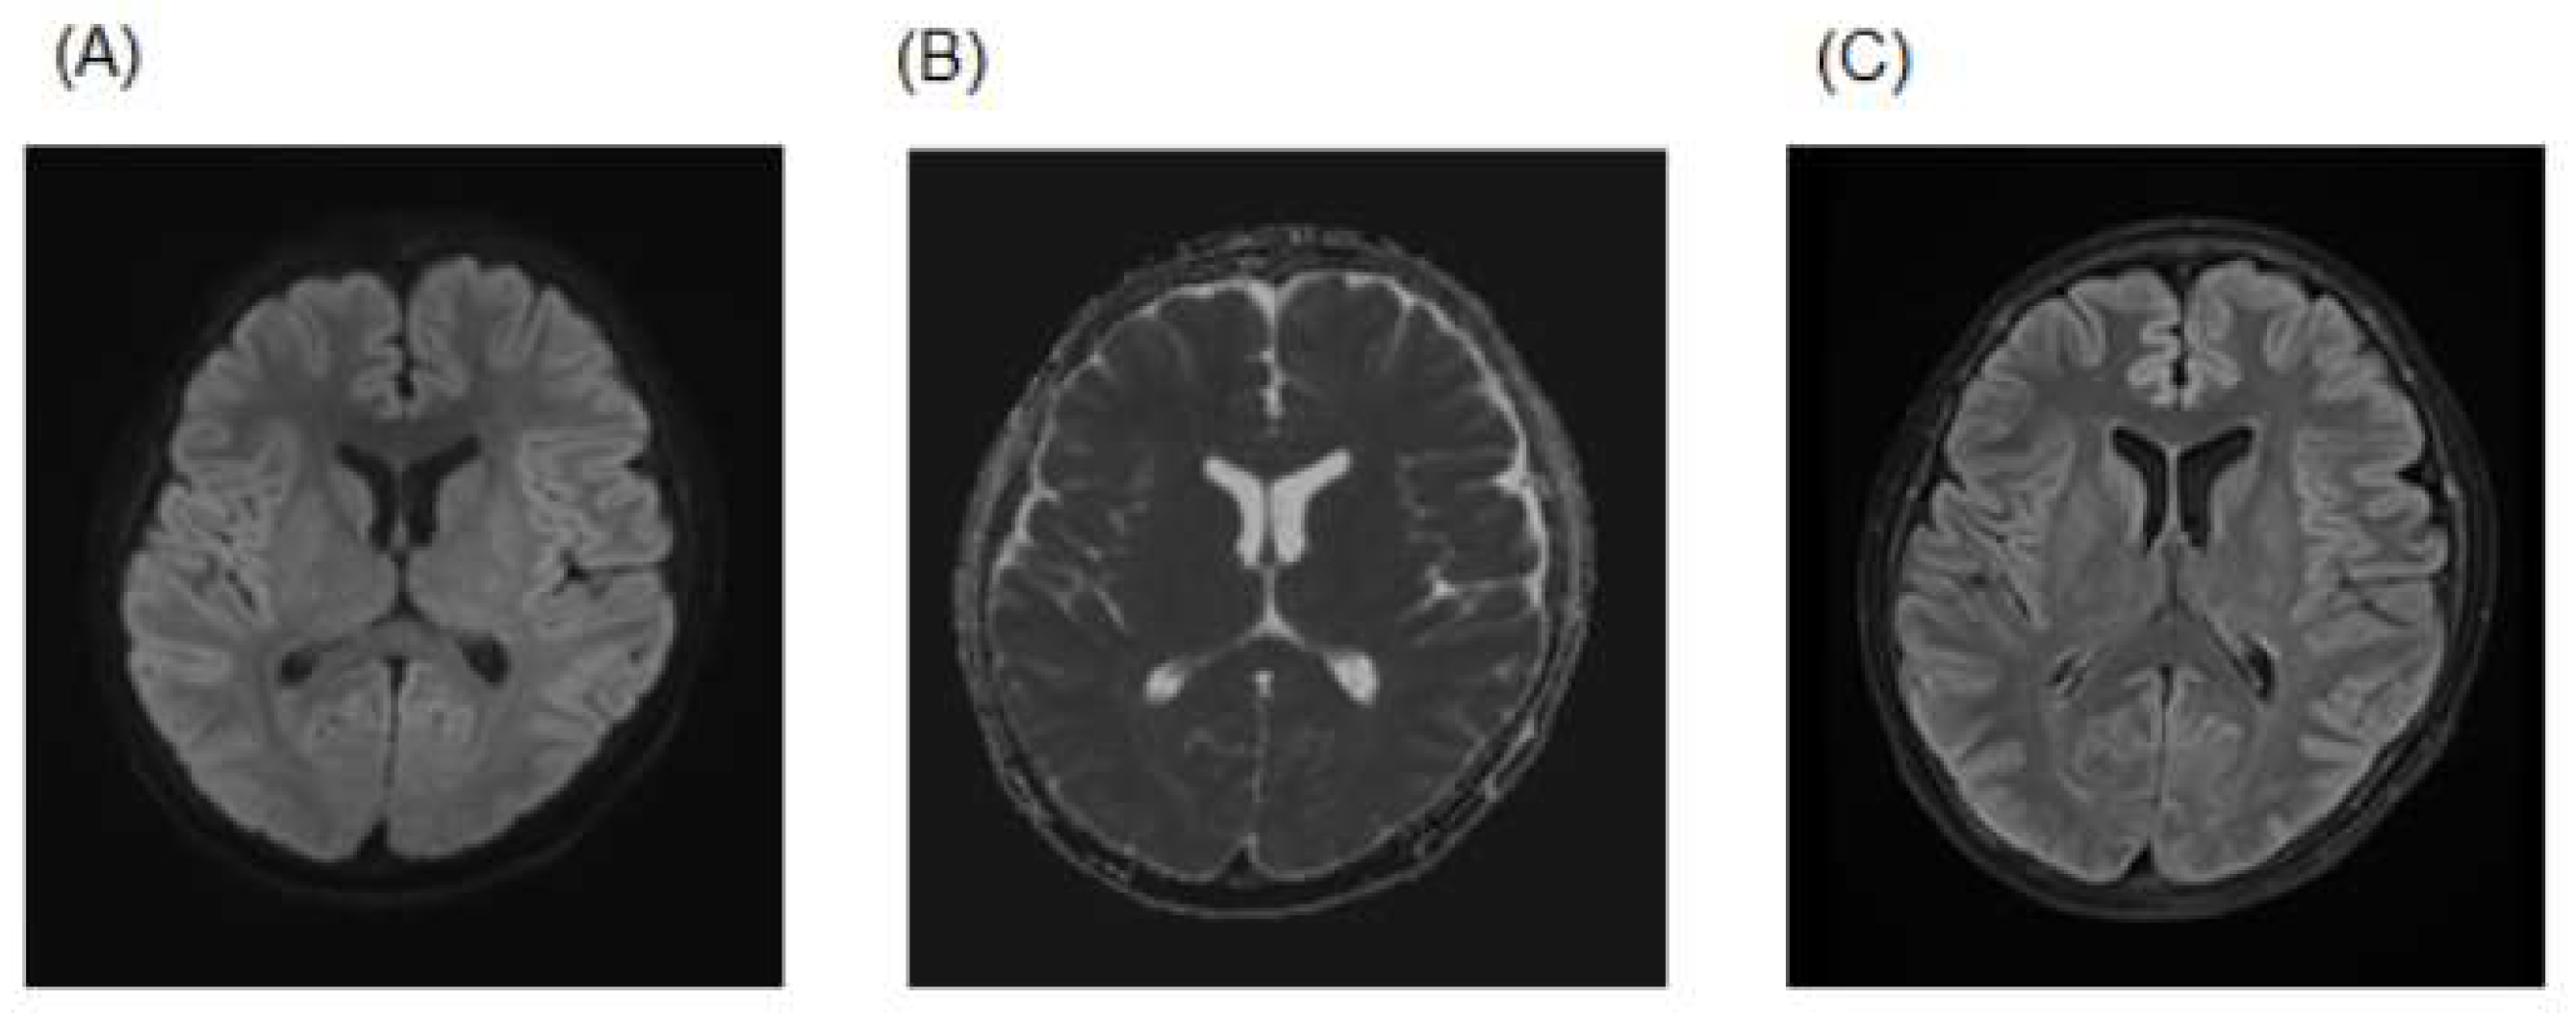

We suspected psychiatric symptoms due to intracranial disease based on the following features: (1) prolonged psychiatric symptoms, (2) a young age, (3) no diurnal fluctuation in psychiatric symptoms, (4) atypical for delirium and (5) no history of drug use that could have caused the psychiatric symptoms. Based on the brain MRI findings, medical history, examination findings and spinal fluid findings, he was considered to have psychiatric symptoms caused by MERS. Psychiatric symptoms appeared on the third day of illness, with the day of onset of COVID-19 as the first day of illness, but he began to improve on the eighth day of illness with symptomatic treatment alone. Brain MRI on the tenth day showed that the abnormal findings on admission had been obscured (Figure 2). On the eleventh day, his psychiatric symptoms and abnormal neurological findings resolved, and he was discharged.

Figure 2.

(A) DWI, (B) ADC map and (C) FLAIR images on the 10th day. The findings seen on admission had been obscured.